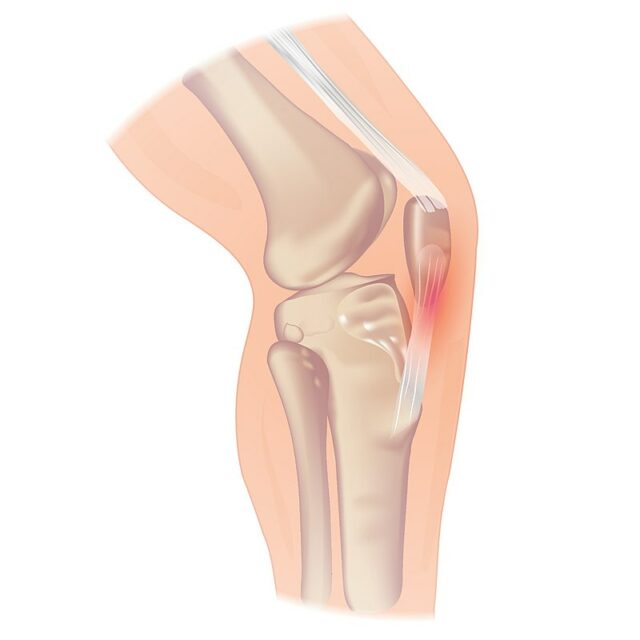

髌骨肌腱病可能发生在髌骨下端,也可能发生在胫骨结节处的肌腱插入处,但这种情况较为罕见。 如果患者报告髌骨底部疼痛,您可能会怀疑是股四头肌腱病。

伦敦皇家医院测试是确认髌腱鞘病变的有效方法,其敏感性高达 88%,特异性高达 98%,可将髌腱鞘病变患者与其他原因引起的膝关节前部疼痛区分开来。

进行测试时,在膝关节完全伸直的状态下,触诊髌腱从近端到远端是否有触痛感。 然后在膝关节屈曲 90 度时再次触摸压痛点。 如果屈曲位疼痛减轻或消失,则测试结果呈阳性。